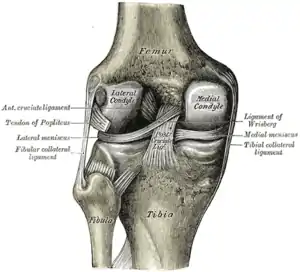

The transverse ligament stretches from the lateral meniscus to the medial meniscus. It passes in front of the menisci. It is divided into several strips in 10% of cases.[10]: 208 The two menisci are attached to each other anteriorly by the ligament.[19] The posterior (of Wrisberg) and anterior meniscofemoral ligaments (of Humphrey) stretch from the posterior horn of the lateral meniscus to the medial femoral condyle. They pass anterior and posterior to the posterior cruciate ligament respectively.[13][10]: 208 The meniscotibial ligaments (or "coronary") stretches from inferior edges of the menisci to the periphery of the tibial plateaus.

Left knee-joint from behind, showing interior ligaments.